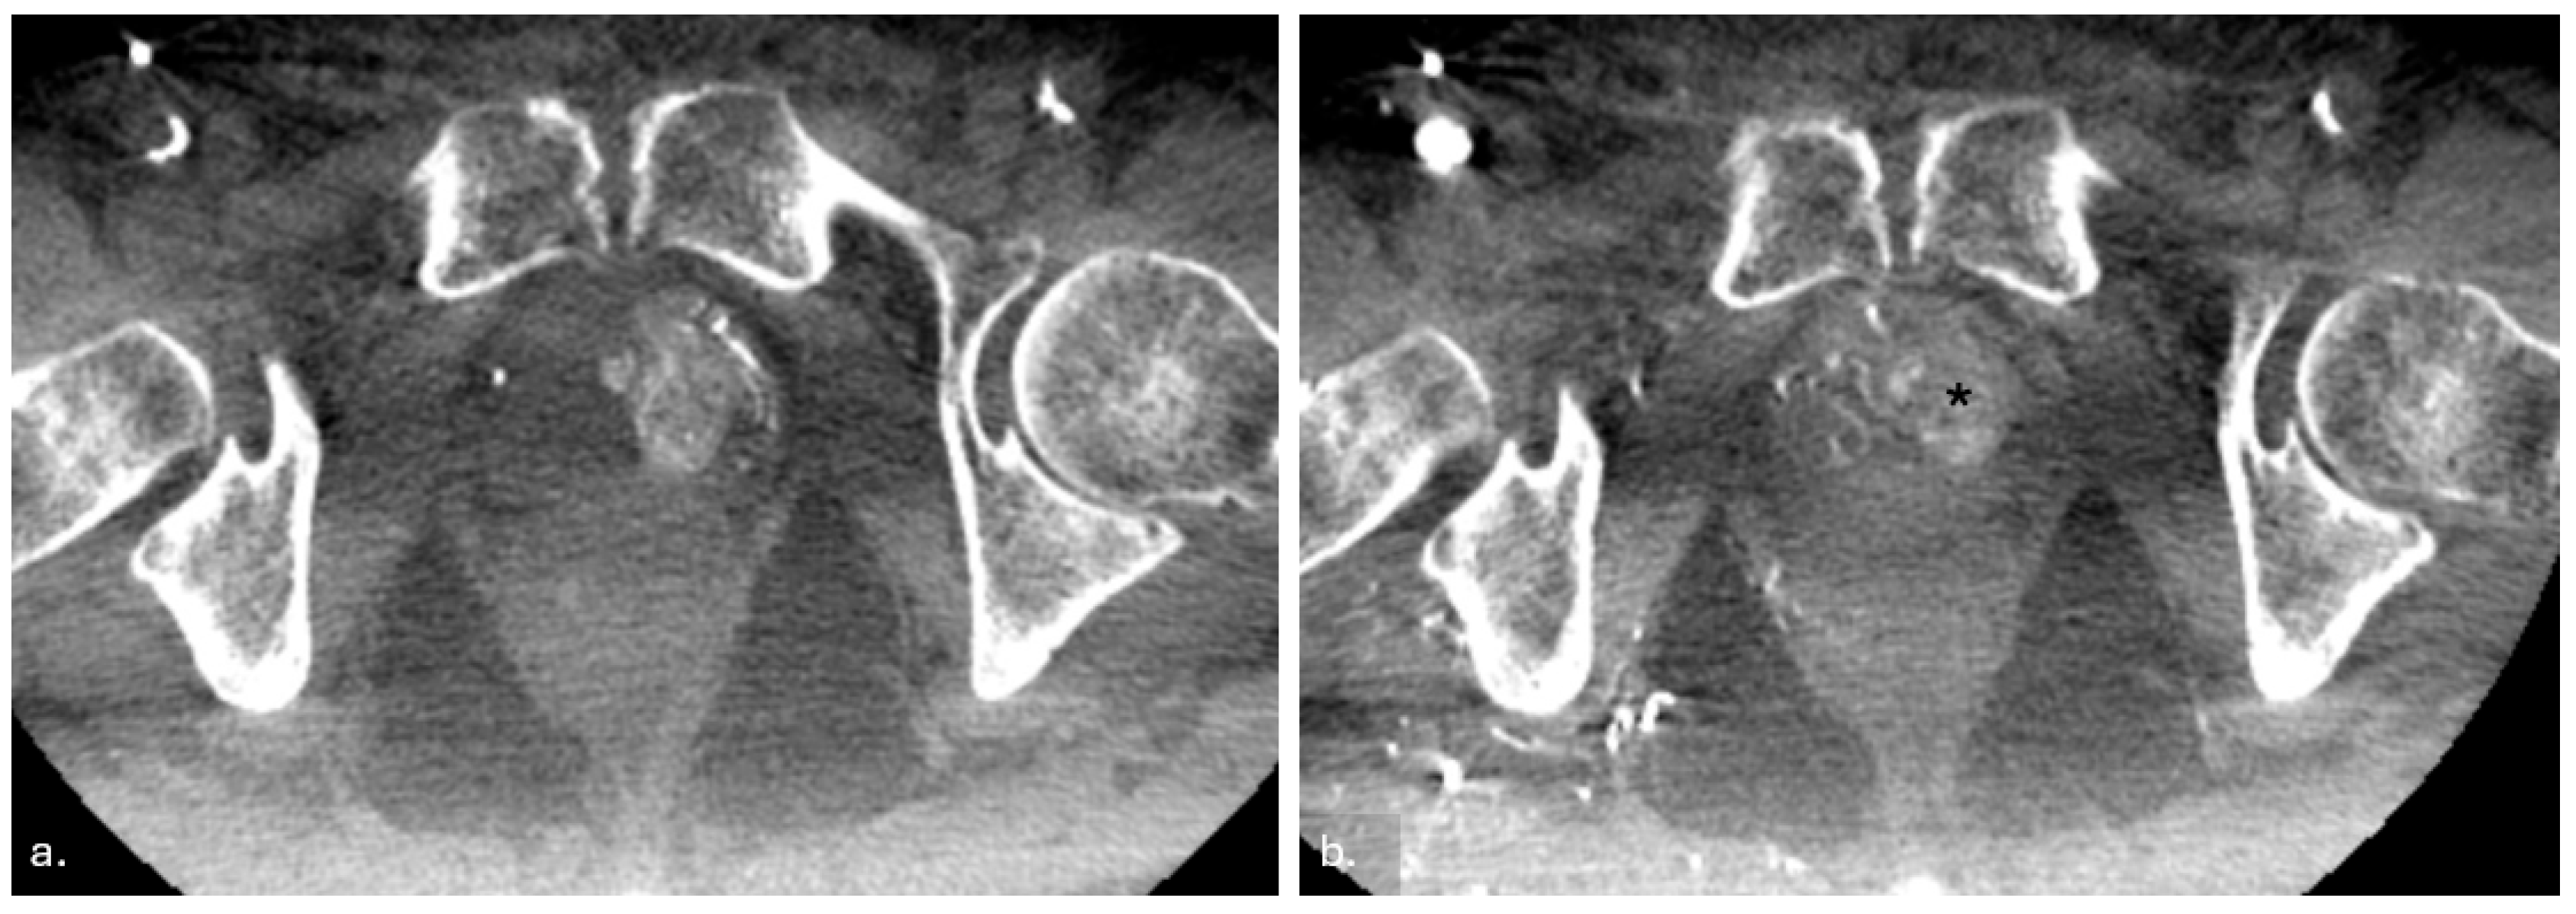

2.3.3. Post-Procedure Imaging and Verification

2.3.4. Postoperative Care and Follow-Up